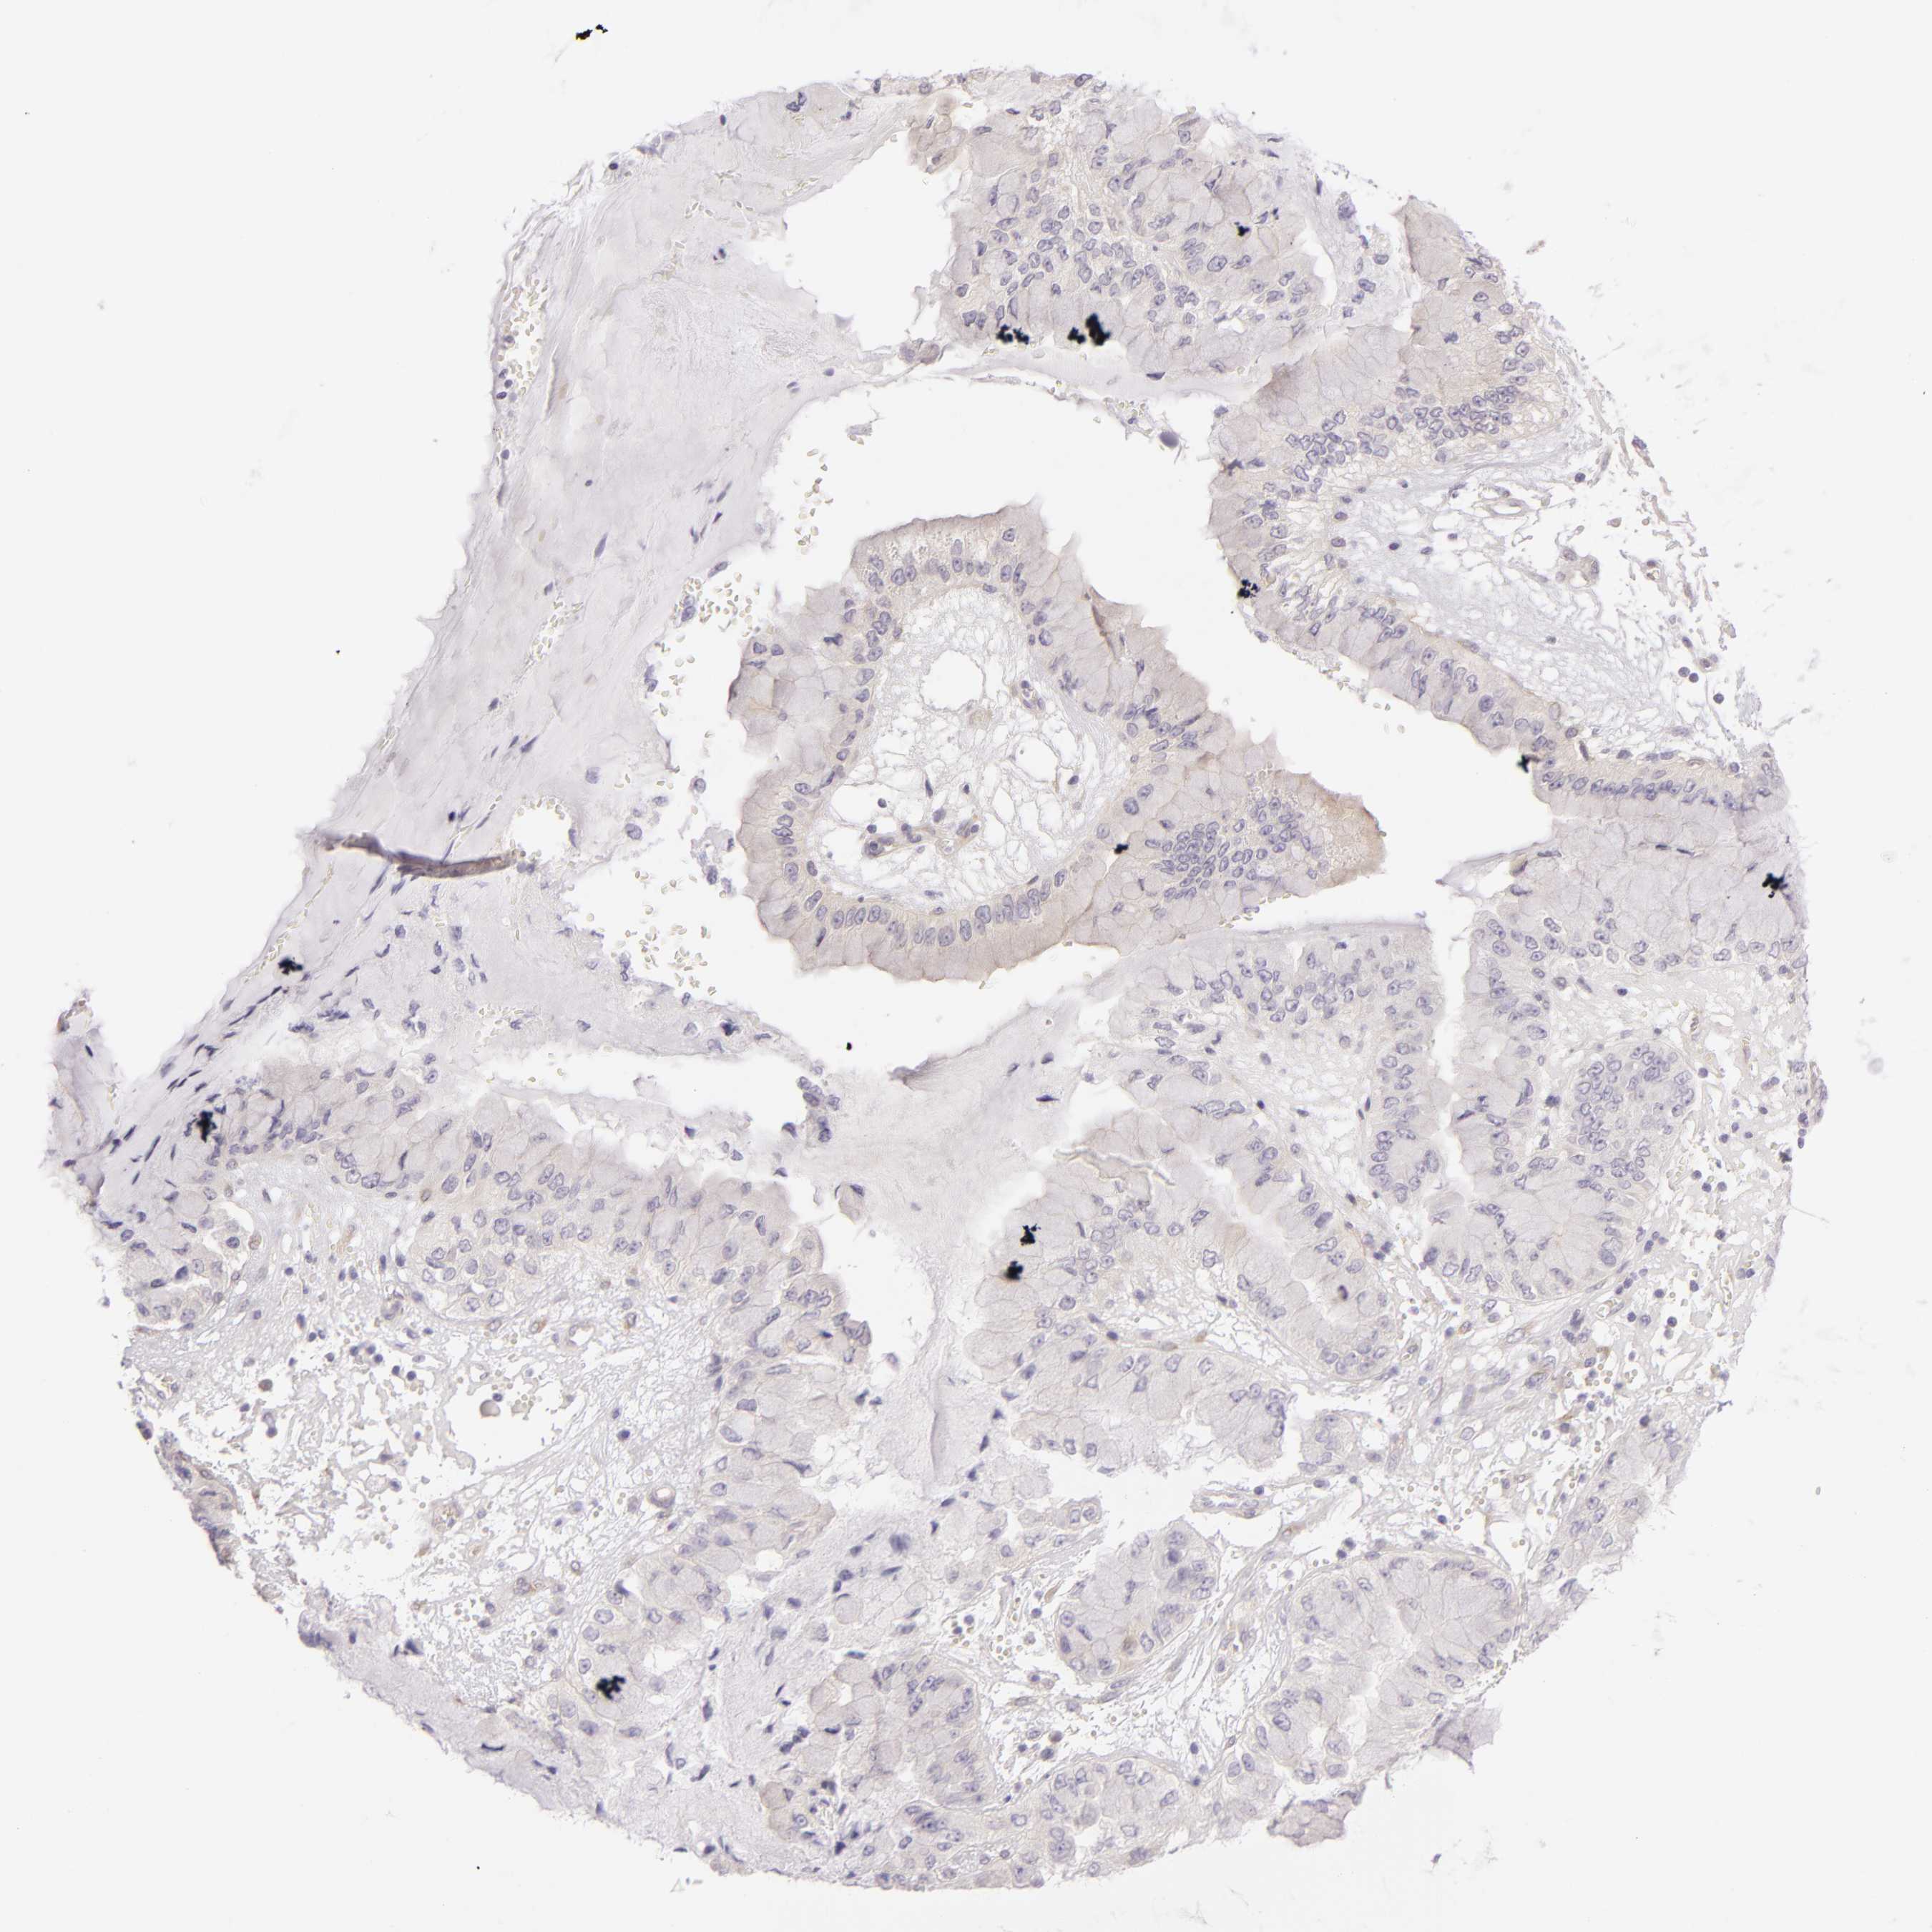

LIVER CANCER - Protein expressioni

A mouse-over function shows sample information and annotation data. Click on an image to view it in a full screen mode. Samples can be filtered based on level of antibody staining by selecting one or several of the following categories: high, medium, low and not detected. The assay and annotation is described here.

Note that samples used for immunohistochemistry by the Human Protein Atlas do not correspond to samples in the TCGA dataset.

Antibody stainingi

Antibody staining in the annotated cell types in the current human tissue is reported as not detected, low, medium, or high, based on conventional immunohistochemistry profiling in selected tissues. This score is based on the combination of the staining intensity and fraction of stained cells.

Each image is clickable and will lead to virtual microscopy that enables deeper exploration of all samples and also displays staining intensity scores, fraction scores and subcellular localization as well as patient and tissue information for each sample.

Antibody HPA001784

Staining

High

Medium

Low

Not detected

Intensity

Strong

Moderate

Weak

Negative

Quantity

>75%

75%-25%

<25%

None

Location

Nuclear

Cytoplasmic/membranous

Cytoplasmic/membranous,nuclear

Carcinoma, Hepatocellular, NOS

Cholangiocarcinoma